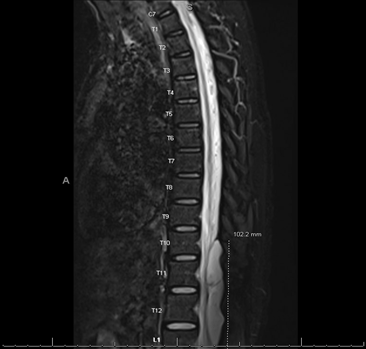

The patient is a 42-year-old female with no pertinent past medical history who presents to neurosurgery spine clinic citing chronic back pain and muscle spasms after failure of conservative treatment including physical therapy, epidural steroid injections, and medications. The patient underwent preoperative imaging using CT and MRI and was diagnosed with a 7.1 cm extradural arachnoid cyst at T11 to L1; Preoperative MRI displayed in figures 1-3 below. This extradural arachnoid cyst was causing compression of the cord and resulting in severe and worsening thoracic back pain and bilateral lower-extremity symptoms including pain, numbness, and loss of balance. The patient was positioned in a lateral decubitus position, lumbar region prepped with chlorhexidine then draped in usual sterile fashion. Lumbar drain was placed, clear CSF obtained, 0.2cc fluorescein in 10cc sterile saline was injected then the lumbar drain was secured with Ioban.

Figure 2: Sagittal STIR MRI without contrast demonstrating a large SEAC spanning from T11 to L1.